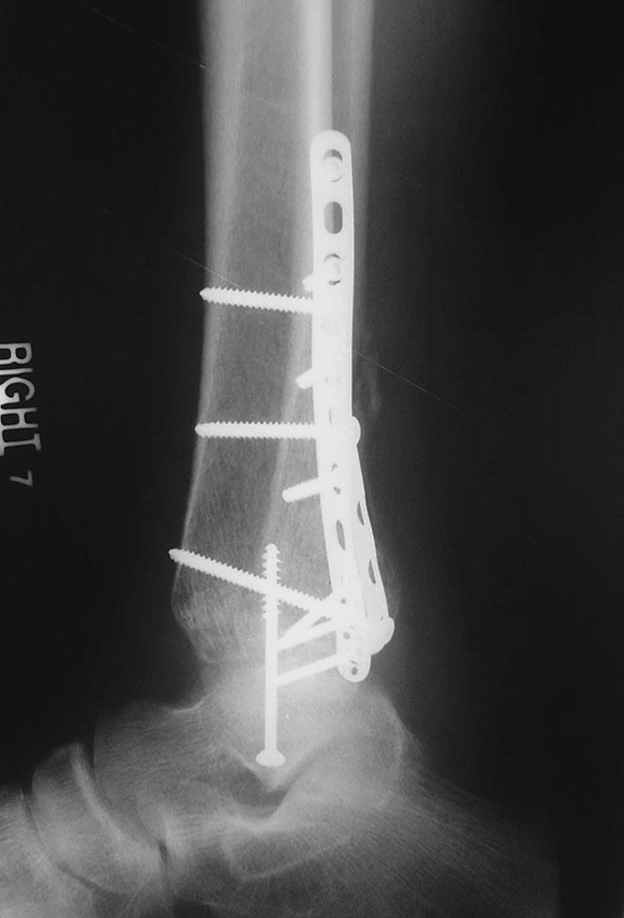

Второй случай сделан из одного разреза

Дж

ЕЧ LISS plate, mininvasive approach - luxurous !